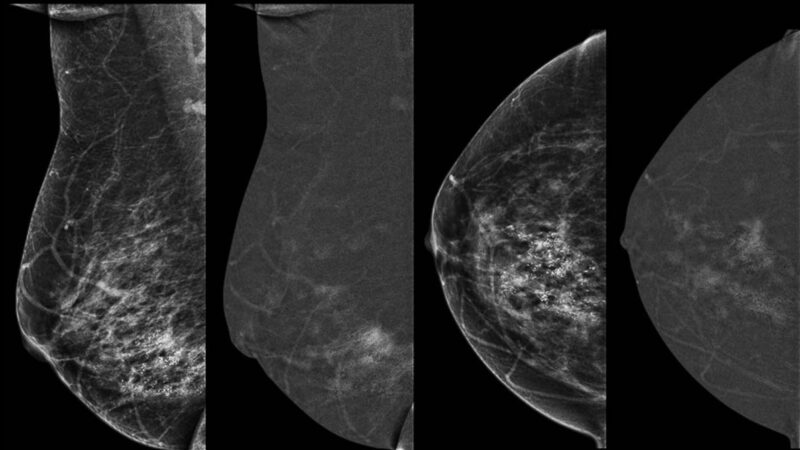

Le 10 juin, le congrès de la Société d'imagerie de la femme (SIFEM) a consacré une session à l’angiomammographie. Corinne Balleyguier, cheffe du service d’imagerie médicale du centre de lutte contre le cancer Gustave-Roussy, à Villejuif (94), a partagé l’expérience de sa structure des biopsies sous angiomammographie. « C’est une technique qui se développe et rend beaucoup de services, surtout dans des bilans rapides, avance-t-elle. À ce jour, 400 procédures de biopsie sous angiomammographie ont été réalisées sur 30 sites dans le monde. »

La première biopsie sous angiommamographie au monde a été réalisée au centre Gustave-Roussy en octobre 2019. « Cette technique reprend le principe de la biopsie guidée sous IRM, c’est-à-dire que l’on a une angiomammographie de référence qui met en évidence des prises de contraste suspectes, indique l’intervenante. À partir du moment où on ne les a pas retrouvées sur les clichés complémentaires de mammographie ou d’échographie, on refait